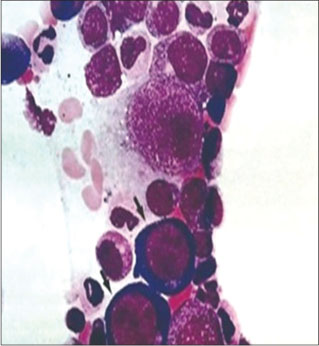

Patient was started with chemotherapy, during the treatment course developed pancytopenia for which bone marrow examination was conducted.

Bone marrow aspirate showed erythroblastopenia with giant pronormoblast with 14% lymphomonocytoid cells suggestive of parvovirus infection [Figure 9]. The patient was detected with raised titers of immunoglobulin M parvovirus antibodies and diagnosis was confirmed with serology.

|?Figure. 9? A 10-year-old male child diagnosed with T-lymphoblastic lymphoma, Bone marrow aspiration showed giant proerythroblast with pale cytoplasmic inclusions suggestive of parvovirus infection (Giemsa, ?1000)|

Parvovirus B19 infection causes severe cytopenia and can mimic a leukemic relapse or therapy-induced cytopenia in patients with hematologic malignancies, and Hence, screening for parvovirus B19 DNA by polymerase chain reaction (PCR) in pediatric patients with ALL and unexplained cytopenia is suggested. Detection of giant pronormoblasts and absence of normal mature erythroid precursors is characteristic of parvovirus infection, on a routine bone marrow examination.